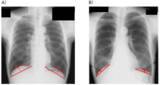

画像:https://newscast.jp/attachments/KenVR3EHodlxm8FTP5qs.pngA)胸部X線画像による、横隔膜ドーム高の測定方法、B)横隔膜ドーム高が低い患者の例...